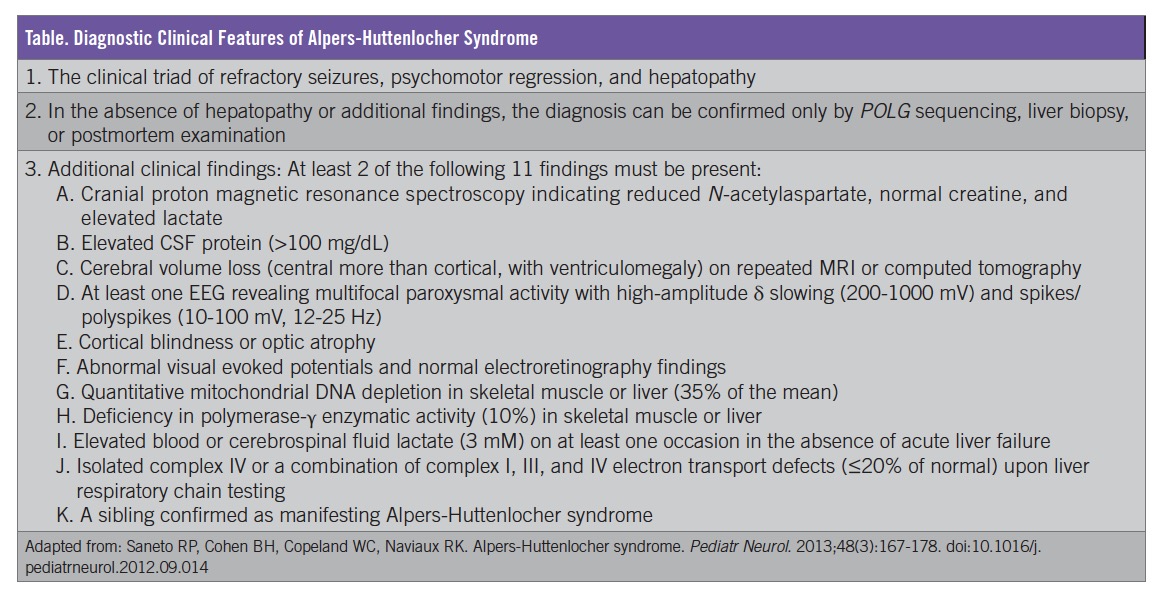

Based on the clinical presentation and the progression of symptoms, including liver dysfunction and abnormal brain MRI findings, our patient received a diagnosis of AHS. Mitochondrial disease process was first suspected when multiple regions of the brain not conforming to vascular territories were noted; the diagnosis of AHS was confirmed once liver dysfunction occurred. Our patient fits the clinical diagnostic criteria, which include the presence of the classical triad (liver dysfunction, intractable seizures, and developmental delay/regression) along with 2 of 11 additional clinical findings (Table).